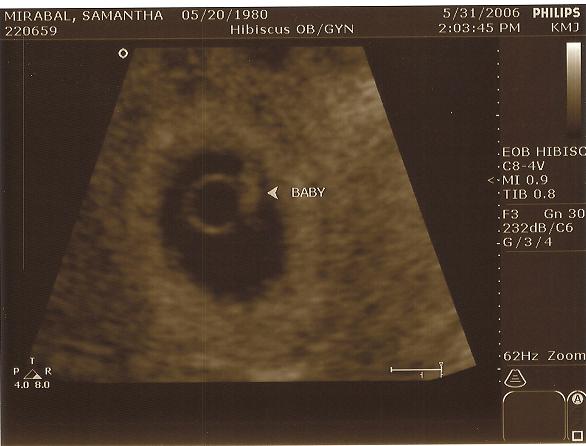

The ultrasound below dated the baby at 6 weeks, 3 days.  Our due date is estimated at 1/21/07.

6 weeks 3 days -- 5-31-0602